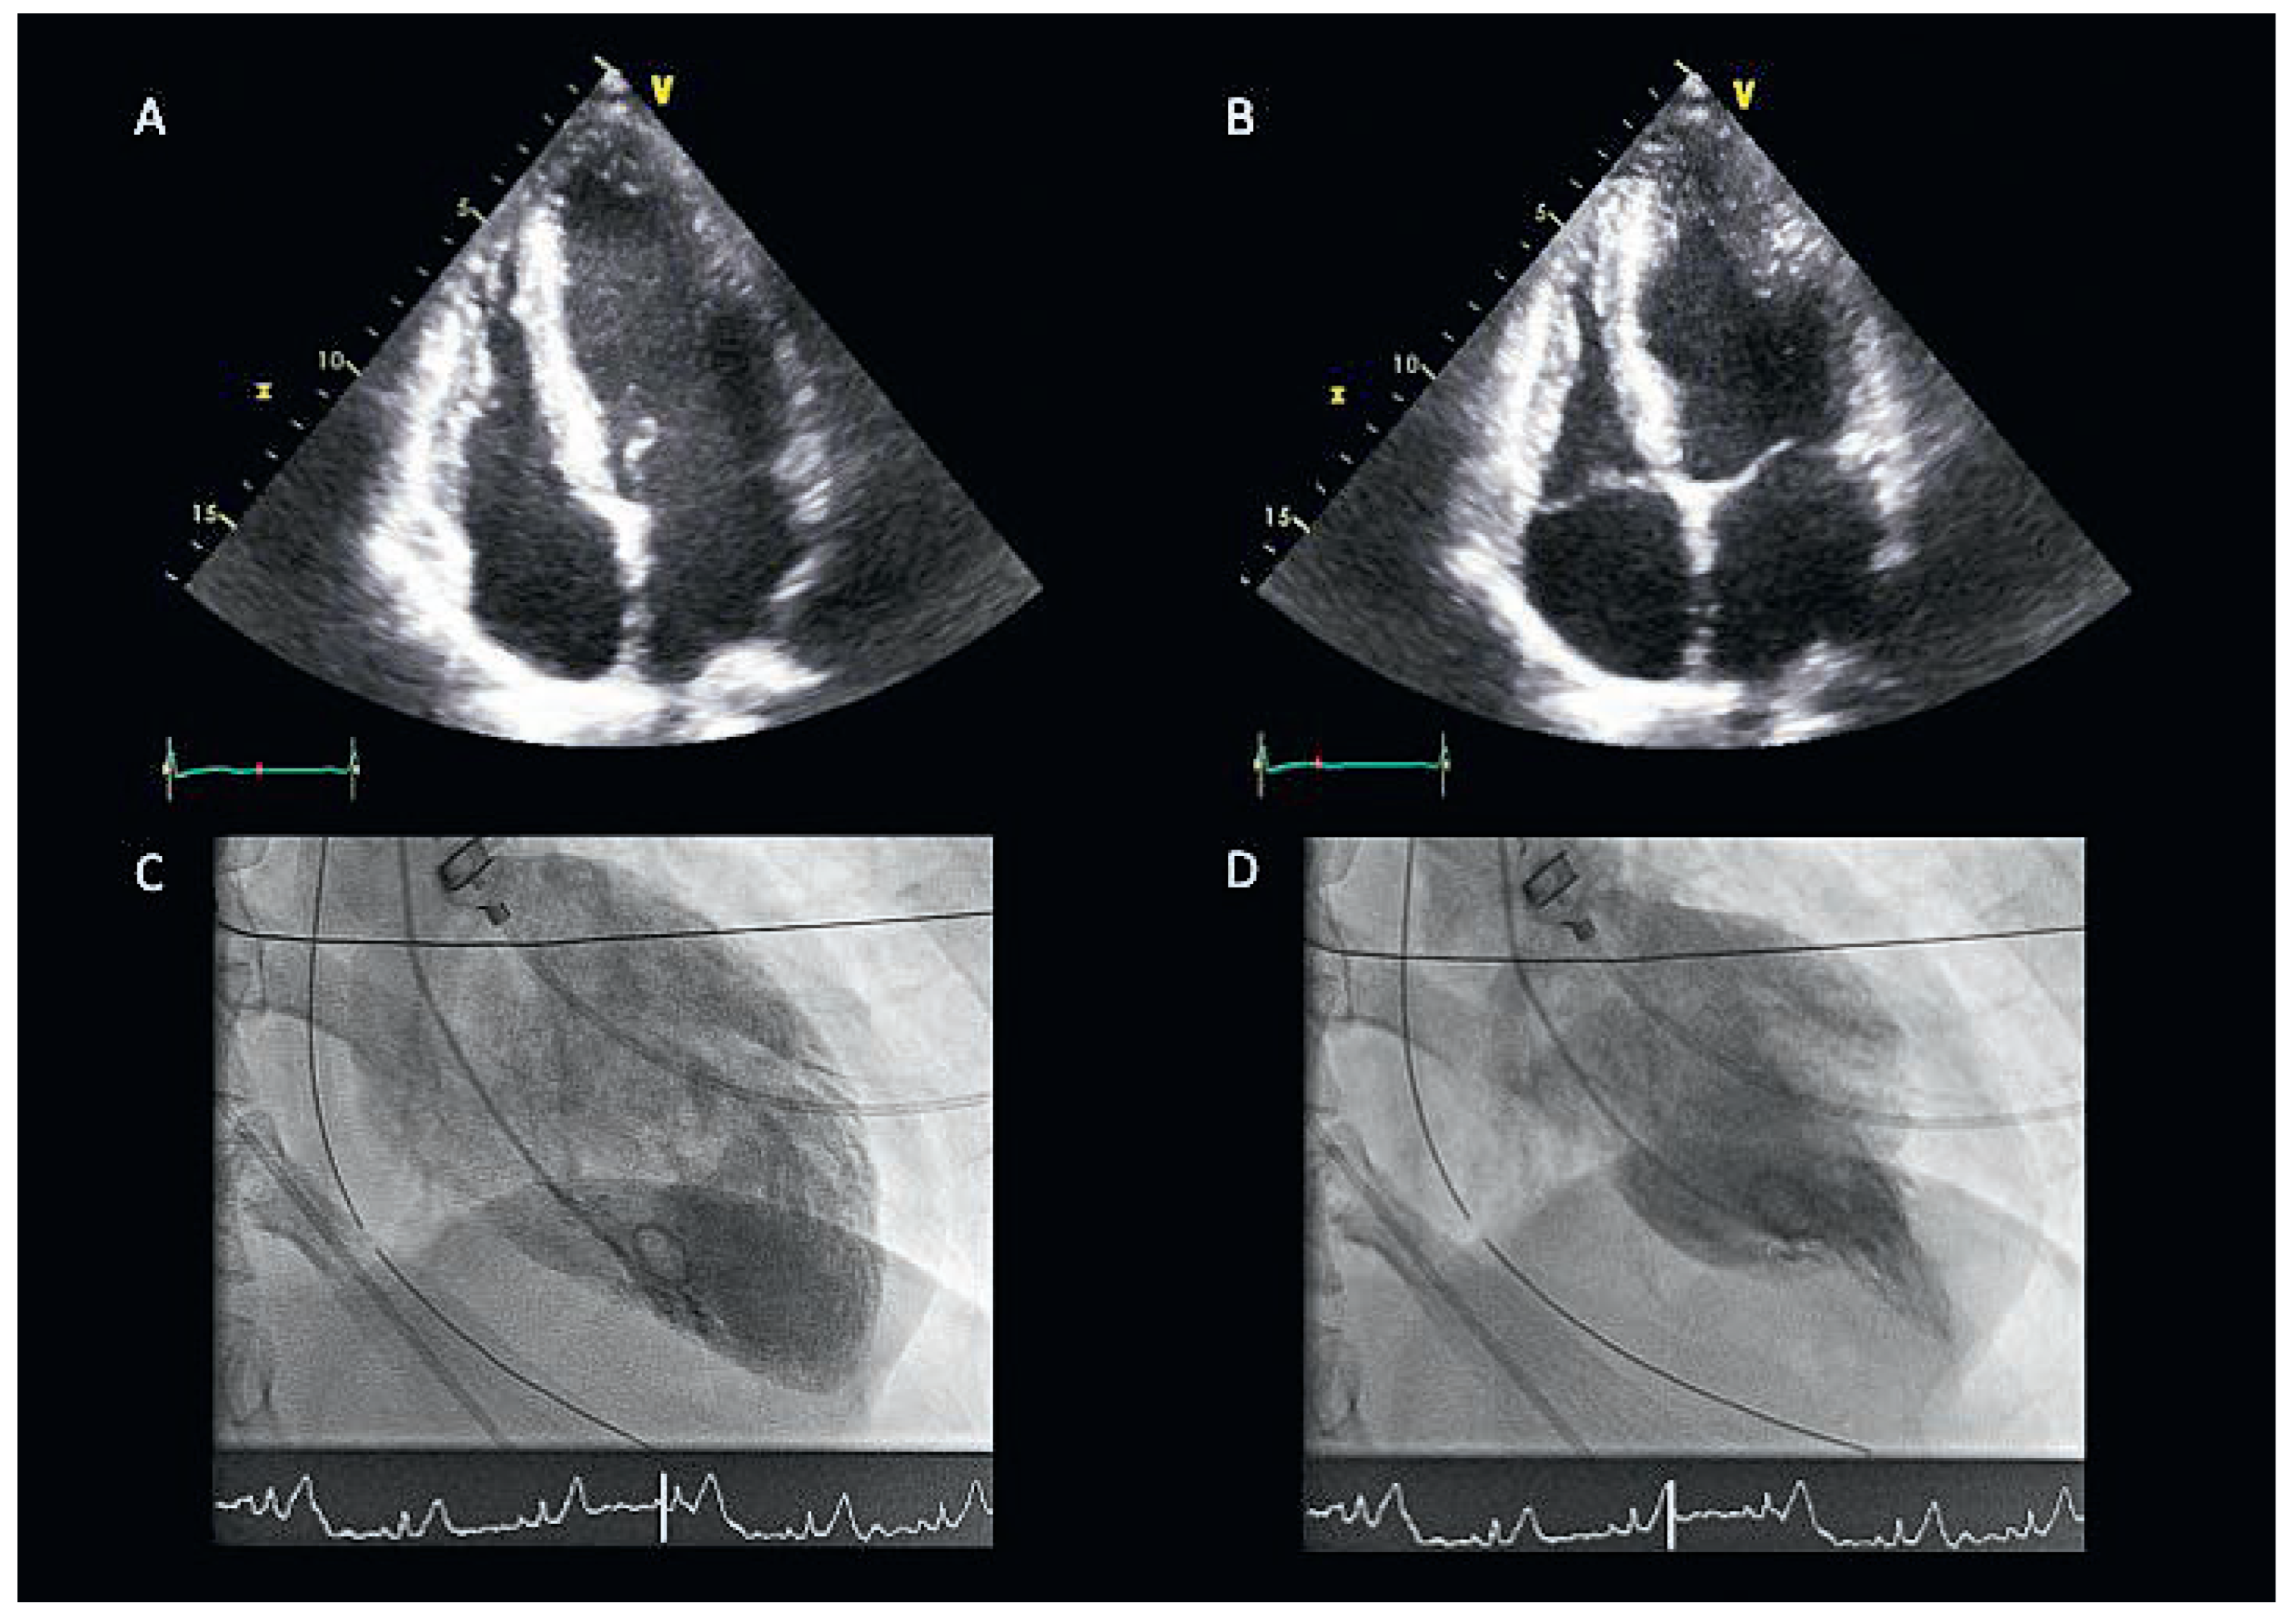

Gunshot Reversed the Tako-Tsubo

Perrin, N.; Stauffer, J.-C.; Froidevaux, L.; Goy, J.-J. Gunshot Reversed the Tako-Tsubo. Cardiovasc. Med. 2017, 20, 24. https://doi.org/10.4414/cvm.2017.00454